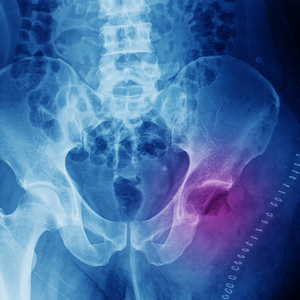

Krebs ist eine Krankheit, die weltweit Millionen von Menschen betrifft und deren Auswirkungen verheerend sein können. Die Diagnose Krebs kann ein Schock sein und stellt sowohl für Betroffene als auch für ihre Angehörigen eine enorme körperliche, emotionale und finanzielle Belastung dar. Während die konventionelle Krebstherapie in Form von Operation, Bestrahlung und Chemotherapie oft als Standardbehandlung angesehen wird, suchen immer mehr Menschen nach alternativen Behandlungsmethoden, um ihre Heilungschancen zu verbessern und die Nebenwirkungen der herkömmlichen Therapien zu reduzieren. Eine vielversprechende Option, die immer mehr an Bedeutung gewinnt, ist die begleitende Frequenztherapie.

Die Idee der Frequenztherapie basiert auf der Annahme, dass jede Zelle und jedes Organ im Körper eine eigene Schwingung oder Frequenz hat. Bei einer Krankheit wie Krebs ist diese Frequenz gestört, was zu einer Fehlfunktion der Zellen führt. Die begleitende Frequenztherapie versucht, diese gestörten Frequenzen mithilfe von elektrischen Impulsen oder elektromagnetischen Wellen auszugleichen und somit die Selbstheilungskräfte des Körpers zu aktivieren.

Die Anwendung von Frequenztherapie in der Krebstherapie ist nicht neu. Schon in den 1920er Jahren experimentierte der Arzt Royal Rife mit elektrischen Frequenzen, um Tumorzellen zu zerstören. In den letzten Jahren hat die Forschung in diesem Bereich jedoch erhebliche Fortschritte gemacht und immer mehr Studien belegen die Wirksamkeit der begleitenden Frequenztherapie bei der Behandlung von Krebs.